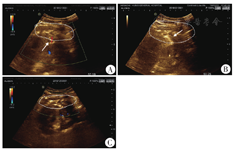

注:A:注射前,箭头所示为出血区域;B:超声下聚桂醇注射,呈高回声影;C:注射后超声影像

治疗经过:内分泌科初步诊断:(1)2型糖尿病;(2)肾病综合征,糖尿病肾病?;(3)高血压3级。为进一步明确蛋白尿病因,在强化降压治疗后,于2018年12月11日行肾穿刺活检。考虑血压、年龄和轻度肾功能异常等因素,患者属于肾活检高危人群[1]。肾活检过程中采用18G穿刺针取材,成功获取2条肾组织。肾活检术后12 h出现腰部剧烈疼痛、出冷汗,复查血红蛋白73 g/L,复查肾脏B超未见明显血肿,给与补液、止血、输血、去甲肾上腺素等治疗。肾活检术后24 h复查血红蛋白58 g/L,伴休克征象(BP 92/57 mmHg,四肢冰冷)。急诊行选择性肾动脉造影+必要时选择性肾动脉栓塞治疗。术中口头报告未见右肾动脉及分支造影剂外溢。造影后血压稳定(去甲肾上腺素维持),输注4 U红细胞后复查血红蛋白62 g/L,肾活检术后48 h复查血红蛋白57 g/L,考虑仍有活动性出血。经超声介入科会诊,多普勒超声明确血肿区域和范围,在超声引导下18G介入穿刺针置入血肿区域,快速注入聚桂醇(团注),每次10 ml,沿血肿上下极共注射30 ml聚桂醇(见图1)。超声介入术后再次输注红细胞4 U,聚桂醇注射24 h后血红蛋白恢复至91 g/L,撤减去甲肾上腺素,未出现异常临床表现。聚桂醇注射后48 h血红蛋白再次轻度下降至84 g/L,血压稳定,并再次给予血肿区域注射聚桂醇20 ml。第2次注射聚桂醇后72 h内多次复查血红蛋白>94 g/L,提示成功止血。患者血红蛋白动态变化见图2。肾活检病理报告:光镜下最大切面见18个肾小球,其中3个球性废弃,2个节段硬化。余肾小球正切体积增大(见图3A)。系膜细胞和基质轻-中度增生。轻度肾小管间质慢性病变,管腔内少量蛋白管型,有间质纤维化(见图3B)。入球小动脉节段透明变性。免疫荧光阴性。电镜下见毛细血管基底膜均质性增厚,厚度约600 nm,未见明显电子致密物沉积(见图3C)。综合意见:(1)糖尿病肾病IIa型(轻度系膜增生);(2)微小病变型肾小球病?